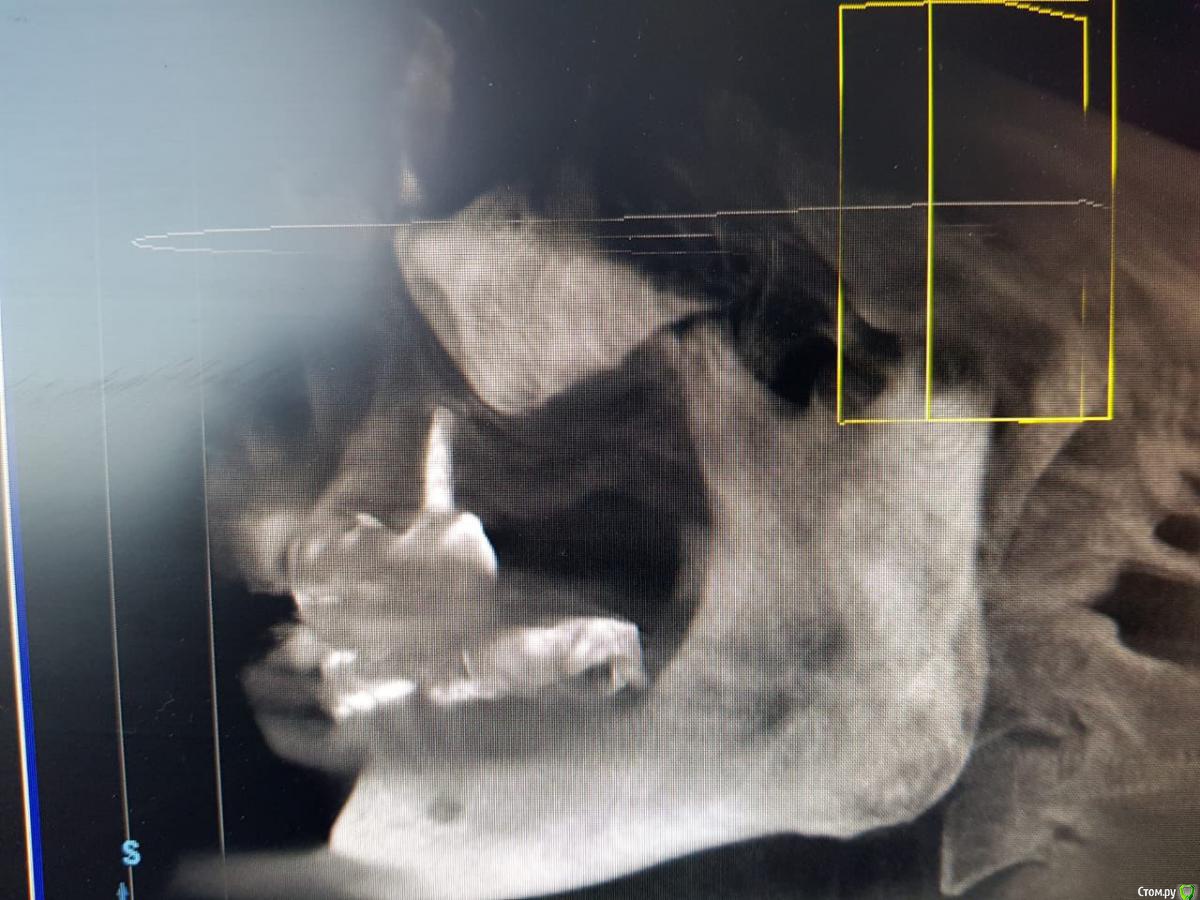

Sunshine Опубликовано 14 марта, 2019 Поделиться Опубликовано 14 марта, 2019 Уважаемые, врачи!Моему отцу 2,5 года назад установили импланты (в другом регионе), и сделали мост, "зацепившись" за живой зуб и имплант...Его ничего не беспокоило до недавнего времени. Теперь вся эта конструкция начала ходить ходуном ... приносит ему боль, естественно полноценно кушать не может.Обратившись в стоматологию по новому месту жительства, стоматологи сообщили, что так делать нельзя ни при каких обстоятельствах, и что надо все снимать, оставшиеся зубы удалять, ждать пока рассосется образовавшаяся киста в районе существующего импланта, и устанавливать новые импланты. Соответственно, вопрос. Так как отец в пенсионном возрасте, то крайне боится вообще остаться без зубов, для него это трагедия. Какие существуют варианты развития событий в нашей ситуации в "щадящем" режиме, но чтобы было все грамотно и четко сделано, дабы больше не возвращаться к вопросу зубов на верхнем ряду. p.s врач который устанавливал данную конструкцию сказал чтоб приезжали-он все поправит, но я его уже не отпускаю, потому что думаю это снова на пару лет...а дальше только хуже... Ссылка на комментарий

kramer Опубликовано 14 марта, 2019 Поделиться Опубликовано 14 марта, 2019 Если нужен несъемный протез, тогда надо удалять все зубы и прежний имплантат, одномоментно ставить 4-6-8 имплантатов (надо более детально изучать случай), временный несъмный протез в день операции или через несколько дней. Ссылка на комментарий

kramer Опубликовано 14 марта, 2019 Поделиться Опубликовано 14 марта, 2019 а что возможно сделать, не прибегая к удалению оставшихся зубов? Имеет ли смысл оставлять их? Какие последствия? Зубы верхней челюсти несостоятельны, сохранить нельзя Если на время удаления всей конструкции ставить съемный протез(это я так понимаю снимаются на ночь и в стаканчик? )), то это же только на то время пока не приживутся новые имплантаты? (примерно 3-6 месяцев) Временный протез несъемный, прикручивается в день операции или через несколько дней (при условии, что первичная стабильность имплантатов хорошая. Если нет, тогда как по сценарию, который вы написали) и что с кистой? Удаляется вместе с имплантатом Ссылка на комментарий